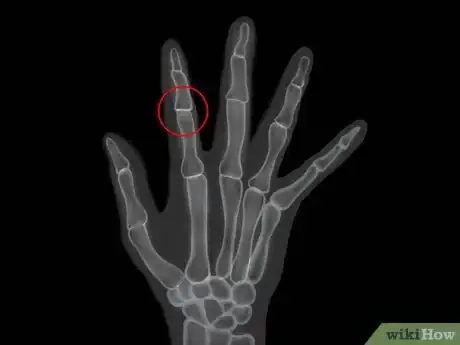

3Learn how rheumatoid arthritis is diagnosed. Rheumatoid arthritis is diagnosed using your signs, symptoms, medical and family history along with a physical exam. Your doctor will then use the diagnosis to create a treatment plan, with the primary goal being reduction of the pain by reducing inflammation and minimizing any damage to the joints.[28] To diagnose rheumatoid arthritis, your doctor will do:

- Lab tests, including x-rays or other imaging of the affected joints